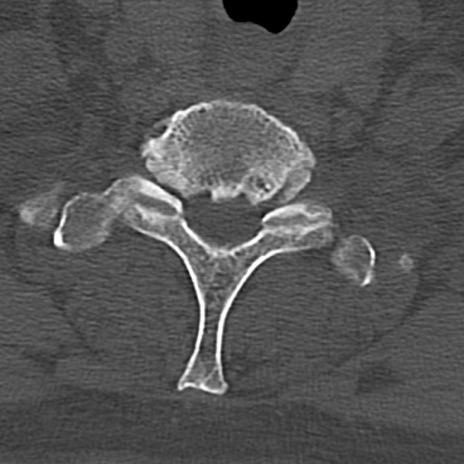

頚椎CT

横断像